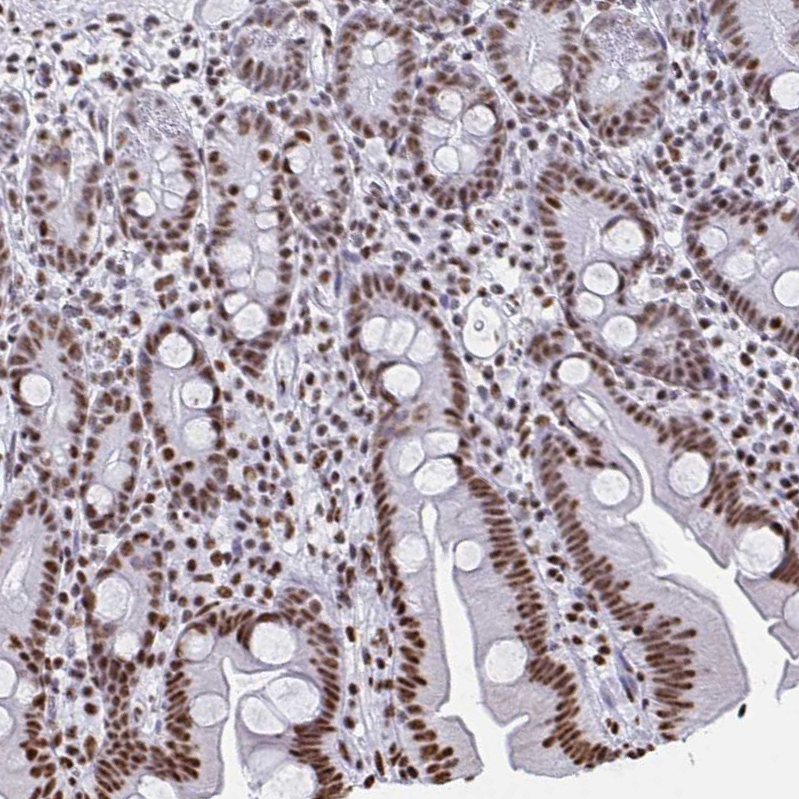

Immunohistochemical staining of human pancreas shows strong nuclear positivity in exocrine glandular cells.